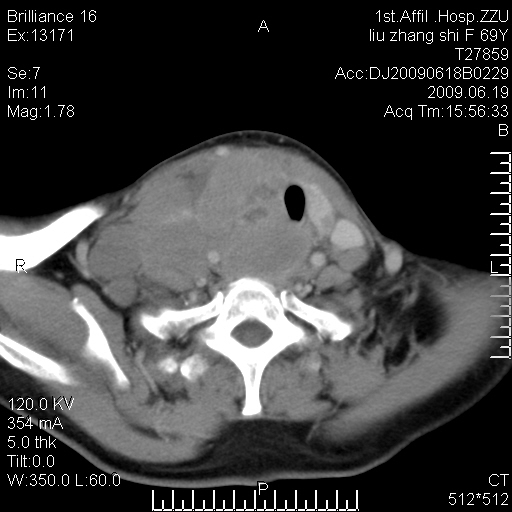

标题: CT26782:女,69岁,颈部占位,3天后公布病理结果。

【病理证实系列】女,69岁,颈部占位,有病理结果,3天后公布。(由于病例时间较久,临床资料不全,请网友见谅)本系列将有几百种常见、少见及罕见病例,均经病理证实。病例资料来自郑州大学第一附属医院。与网友共享,本人有空就发。

甲状腺癌并颈部淋巴结转移。感谢楼主的良苦用心,谢谢。

甲状腺癌并颈部淋巴结转移。

需与鼻咽癌鉴别!

支持甲状腺癌广泛侵及周围结构并颈部淋巴结转移。

鉴别:淋巴瘤、恶性神经源性病变、恶性纤维组织细胞瘤。

病理结果:颈部非霍奇金淋巴瘤。